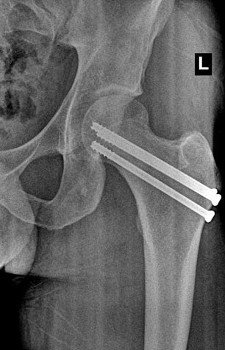

Example X-Ray Images

Repair of Femoral Neck Fracture With Screws